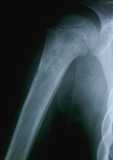

La radiologia dell’omero sinistro rivela un interessamento della diafisi, che presenta piccole aree di osteolisi e una reazione periosteale (fig 1). Gli esami ematochimici sono alterati nel senso della flogosi: VES 13O; PCR 23 mg/, UI/dL, Hb 8,4g/dL; leucociti 8000/mmc (N34%, M5, EO, L61); piastrine 180/mmc. Viene posta la diagnosi di osteomielite, viene effettuata una emocultura (negativa) e iniziata una terapia antibiotica con vancomicina e aminoglicoside.